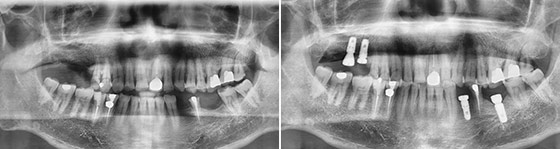

任博士术前通过三维CT扫描,测出患者缺牙部位牙槽骨的高度、宽度、密度,提前预定种植的位置、角度、深度。数字化导板技术,全程导航,完成2颗种植体的植牙手术仅用5分钟,手术全程精准、舒适,手术效果震撼全场。

张叔叔由于年轻时没注意导致多颗牙缺失,导致吃饭咬不动、嚼不烂,在听说任势雄即将来宁亲诊直播种牙后,张叔叔就抱着试试看的心态报了名,没想到幸运的被选中了!